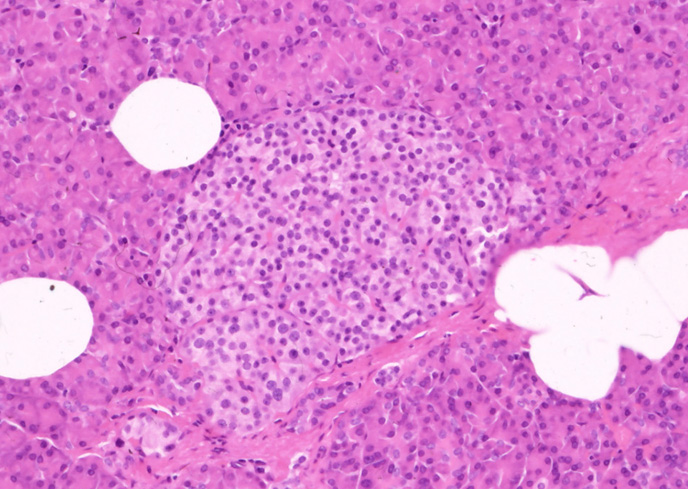

←クリックで大きな画像が見られます。ランゲルハンス島のHE染色像

HE像でも小さめな細胞が辺縁に認められ、おそらくGlucagon産生のA細胞と考えられる。